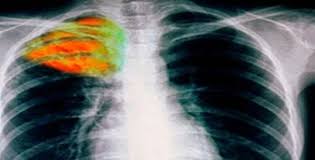

Η φυματίωση, που προσβάλει τον άνθρωπο εδώ και 70.000 χρόνια, εξακολουθεί να υπάρχει και να αποτελεί ακόμη και σήμερα την πρώτη αιτία θανάτου από λοιμώδες νόσημα. Το 1/3 του πληθυσμού της γης έχει μολυνθεί με το μυκοβακτήριο της φυματίωσης το οποίο έχει την μεγαλύτερη προσαρμοστικότητα από όλα τα παθογόνα του ανθρώπου και έχει κοινή εξελικτική πορεία με τον άνθρωπο. Τα παραπάνω ανέφερε στο ΑΠΕ-ΜΠΕ η επίκουρη καθηγήτρια Πνευμονολογίας του ΑΠΘ Κατερίνα Μανίκα με αφορμή ομιλία της με θέμα “Το σύγχρονο πρόσωπο της φυματίωσης” στο πλαίσιο εκδήλωσης για την-Παγκόσμια Ημέρα Φυματίωσης (24 Μαρτίου) που πραγματοποιήθηκε στο νοσοκομείο Παπανικολάου.

“Η φυματίωση εξακολουθεί να υπάρχει παρά τις εξελίξεις που έχουν γίνει στη διάγνωση και τη θεραπεία της. Επίσης υπάρχουν πλέον και μορφές της που είναι ανθεκτικές είτε σε ένα φάρμακο είτε σε περισσότερα. Η αντοχή στα αντιφυματικά φάρμακα είναι αποτέλεσμα αυτόματων και ανεξάρτητων μεταλλάξεων .Η ανθεκτική φυματίωση είναι ένα ανθρώπινο δημιούργημα και οφείλεται στην ανεπάρκεια του θεραπευτικού σχήματος, που ευνοεί την ανάπτυξη των ανθεκτικών στελεχών. Η σύνθετη αντοχή είναι το αποτέλεσμα διαδοχικών μονοθεραπειών. Τα φάρμακα που χρησιμοποιούνται στην πολυανθεκτική είναι ασθενέστερα, ακριβότερα και με περισσότερες ανεπιθύμητες ενέργειες” επισήμανε η κ Μανίκα . Ως παράγοντες της επανάκαμψης της φυματίωσης ανέφερε την μετανάστευση, την λοίμωξη με HIV, την εξασθένιση των προγραμμάτων ελέγχου την εμφάνιση πολυανθεκτικών και εκτεταμένα ανθεκτικών στελεχών.